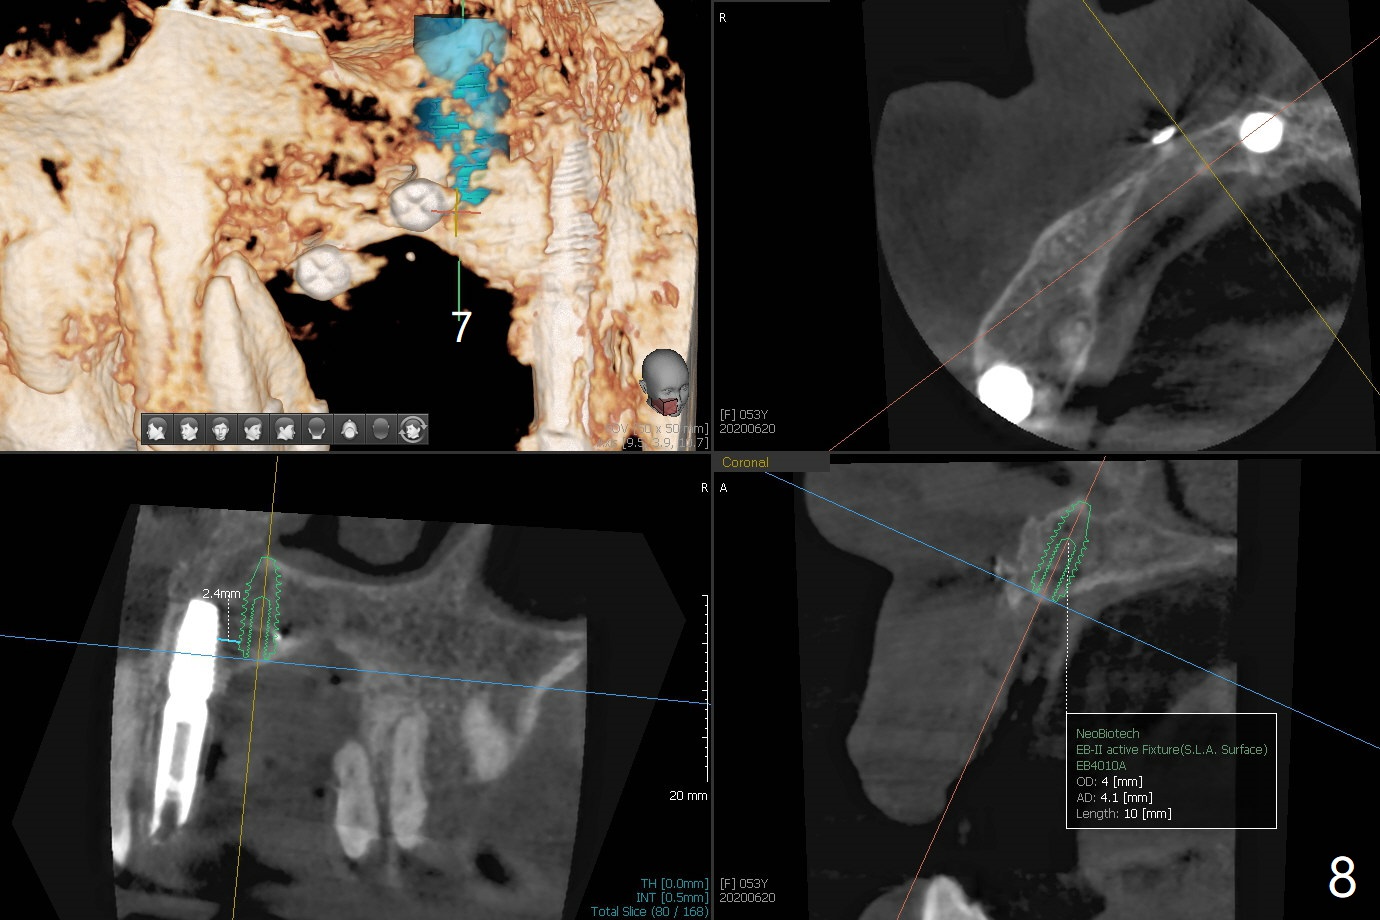

Four months post bone graft with tenting screws at #6 and 7 and implant re-placement at #8, the ridge at #6 and 7 appears to widen slightly, appropriate for narrow implants (Fig.1,2). Guide will be fabricated. The implant at #8 seems to have osteointegrated (Fig.3) with distal gingival recession (Fig.4). One year 5 months later, the tooth #5 is infected with apparently mesial bone loss (Fig.5 *) and papillary erythema and edema (Fig.6). However the pockets are not deep. A gingival embrasure is created between #5 and 6 for self cleansing. The latter does not work. Implants will be placed at #5 and 7 (Fig.7,8).